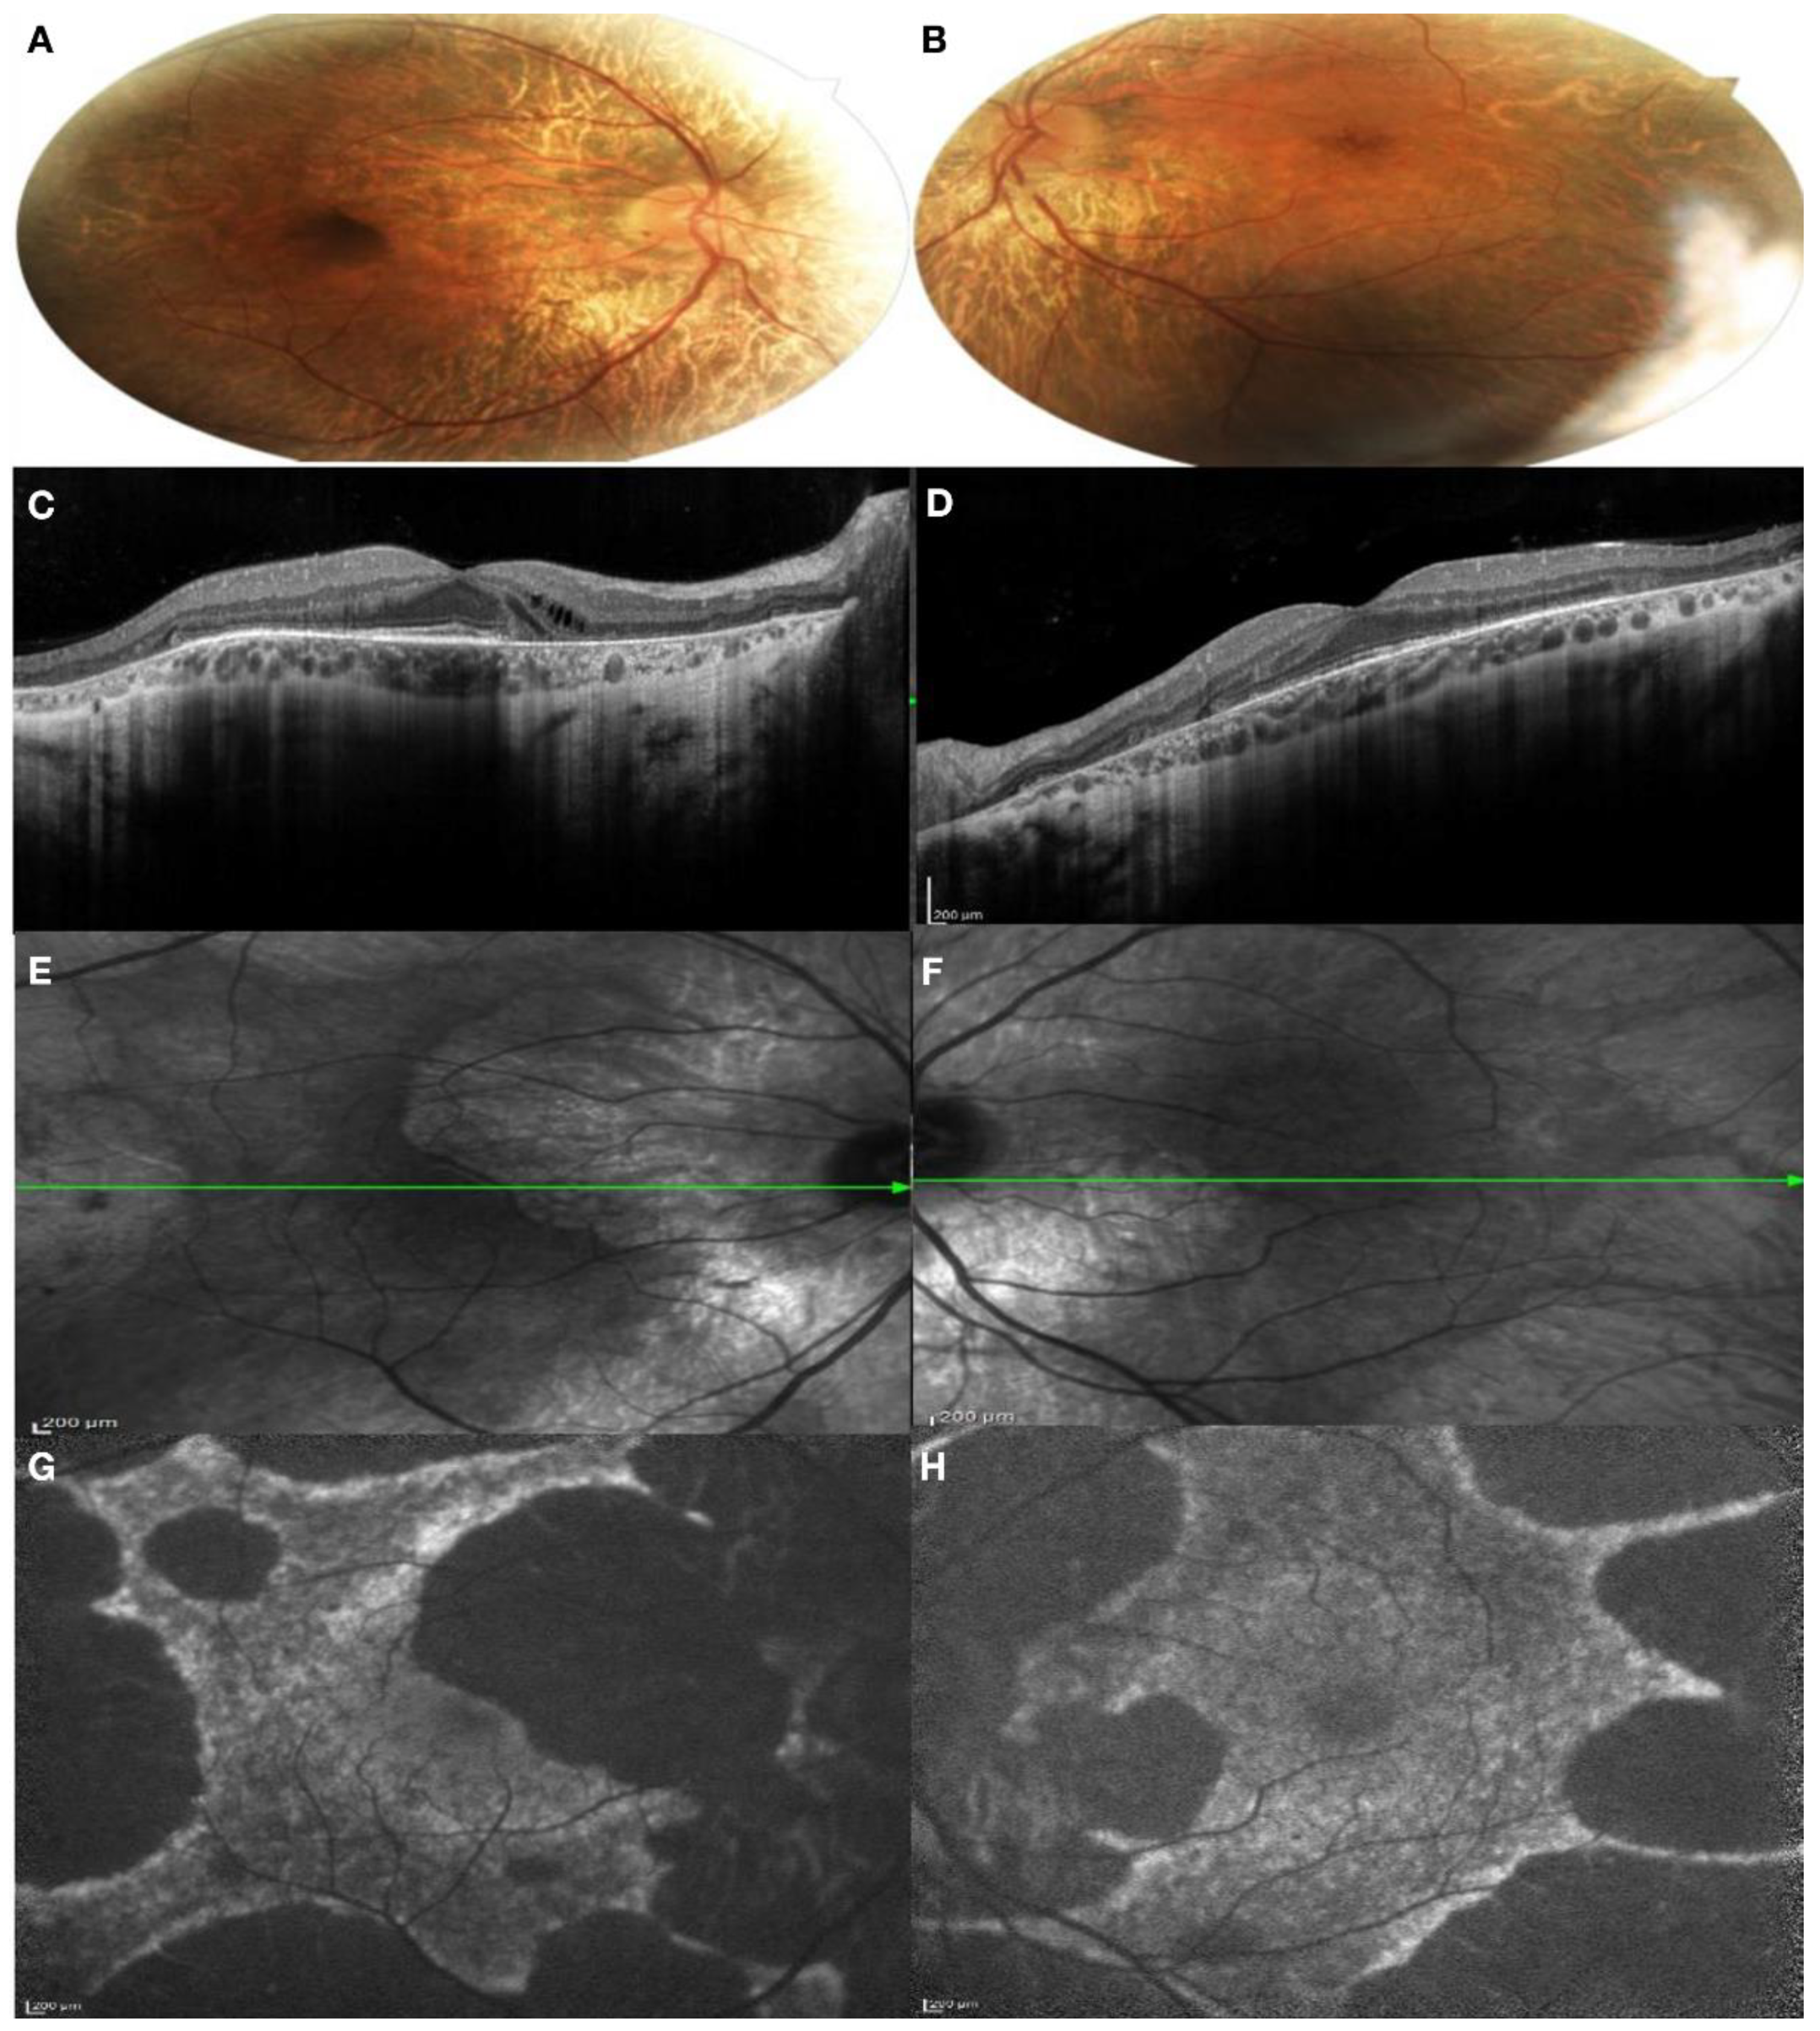

3.1. Clinical Findings